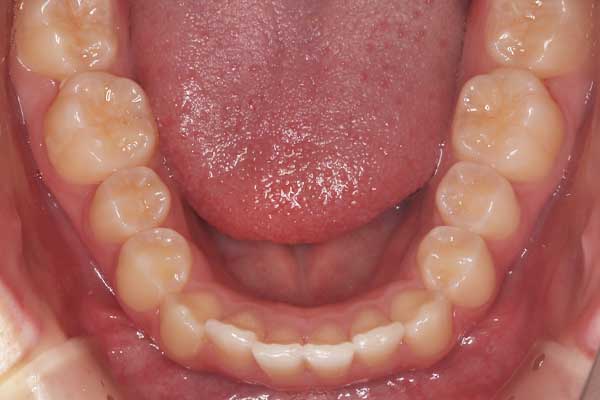

- 治療前